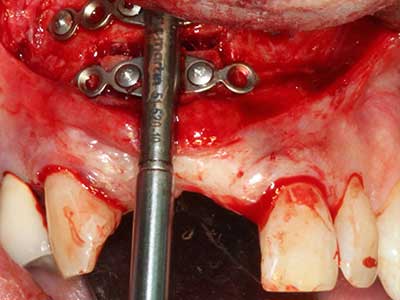

Wie sich in der Vergangenheit gezeigt hat stellt prinzipiell jeder knochenchirurgische Eingriff eine mögliche Indikation für die Piezochirurgie dar. So lässt sich die Präparation des mobilen Segmentes bei der Distraktionsosteogenese (Abb. 23-25) und der Sandwichosteotomie mit speziellen Ansätzen bewerkstelligen, ohne die für den Erfolg beider Techniken essenzielle Blutversorgung des krestalen Anteils zu gefährden (Gonzalez-Garcia, Diniz-Freitas et al. 2008).

Rein kieferchirurgische Indikationen ergeben sich unter anderem in der orthognathen Chirurgie, bei der Genioplastik (Abb. 27-30) sowie der Orbitadekompression bei Patienten mit fortgeschrittener endokriner Orbitopathie bei Morbus Basedow (Ponto, Zwiener et al. 2014). Zudem finden Piezogeräte je nach Klinik Anwendung in der kraniofazialen Chirurgie sowie bei der Entfernung von Schädelbasistumoren.